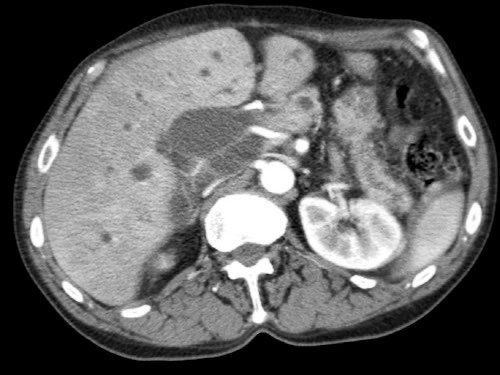

Các hình ảnh axial của cùng bệnh nhân có chú thích.

Hình MIP mặt phẳng đứng ngang này cho thấy một động mạch gan phải thay thế xuất phát từ phía phải của SMA (mũi tên vàng trong A).

Động mạch này đi qua vùng lân cận đầu tụy.

Hình CT axial cho thấy đường đi của động mạch gan phải thay thế phía sau tĩnh mạch cửa (đầu mũi tên vàng) và động mạch gan trái nguyên bản đi phía trước tĩnh mạch cửa (đầu mũi tên xanh lá).

Đây là phát hiện tình cờ ở một bệnh nhân không có bệnh lý tụy.